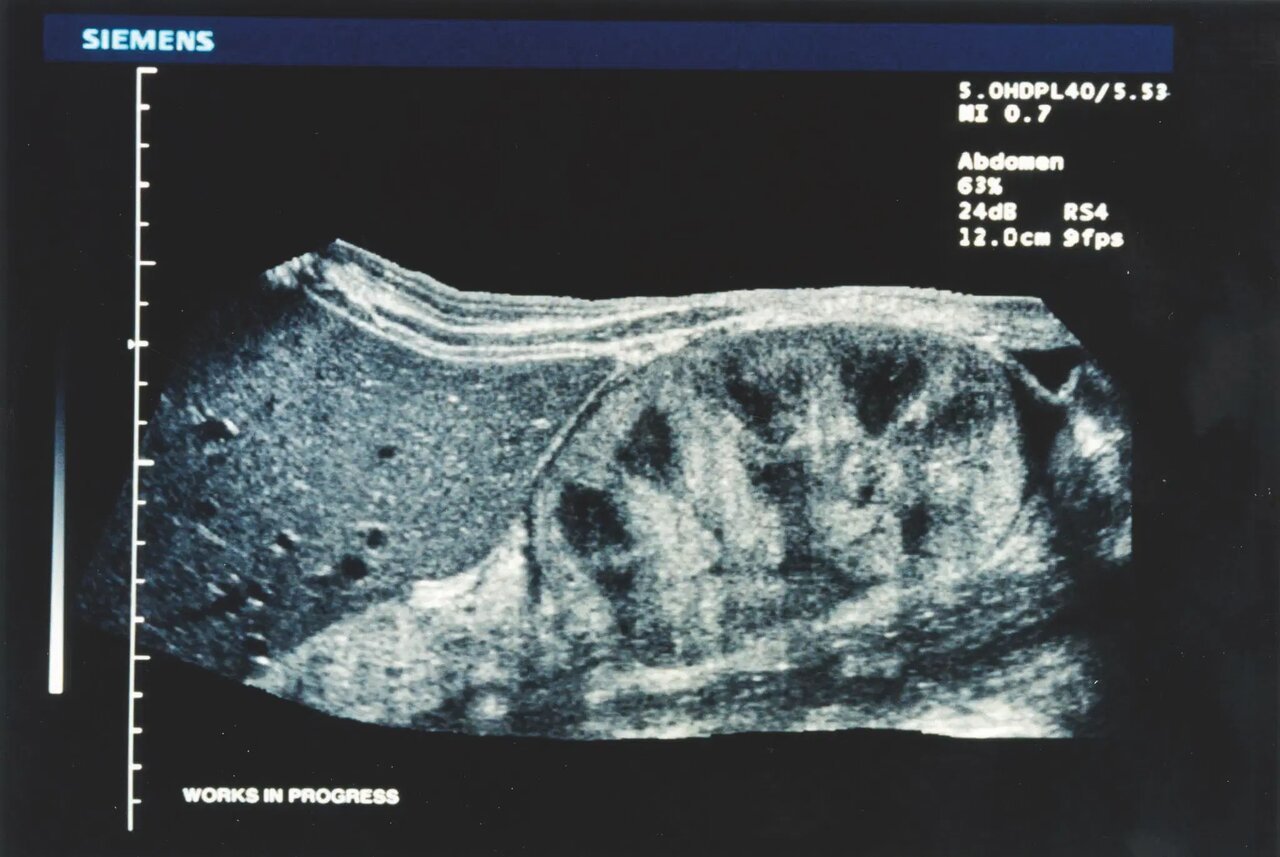

۲۰۰۹

سیستم سونوگرافی بسیار پیشرفته و اسکنر حجم پستان؛ که تصاویر حجمی با وضوح بالا را از پستان به دست میآورد. این سیستم برای استفاده در زنانی با بافت متراکم پستان، امکان تجسم نمای آناتومیک کرونی پستان را فراهم میکند.